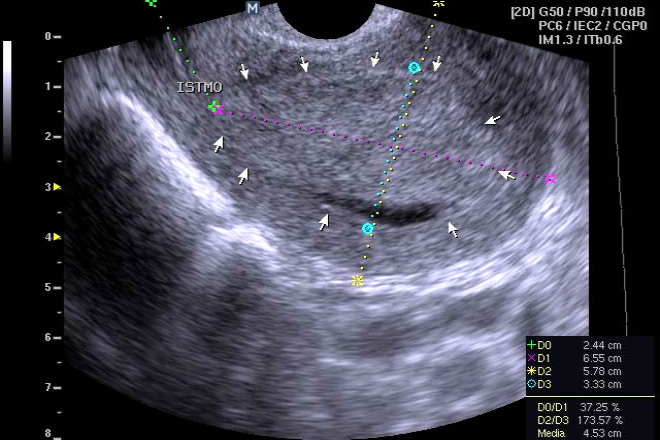

Un estudio propone el uso del ultrasonido Doppler color y espectral para analizar el comportamiento circulatorio arteriolar en pacientes con varicocele y disminución en la cuenta espermática, ofreciendo una alternativa diagnóstica no invasiva para predecir el estado de la cuenta espermática en estos pacientes.

El análisis de los índices de resistencia y pulsatilidad de las ramas capsulares e intratesticulares de la arteria testicular en pacientes con varicocele y controles no mostró diferencias estadísticamente significativas ni correlación con la cuenta espermática. La disposición anatómica de las ramas intertesticulares dificulta su análisis con Doppler color.